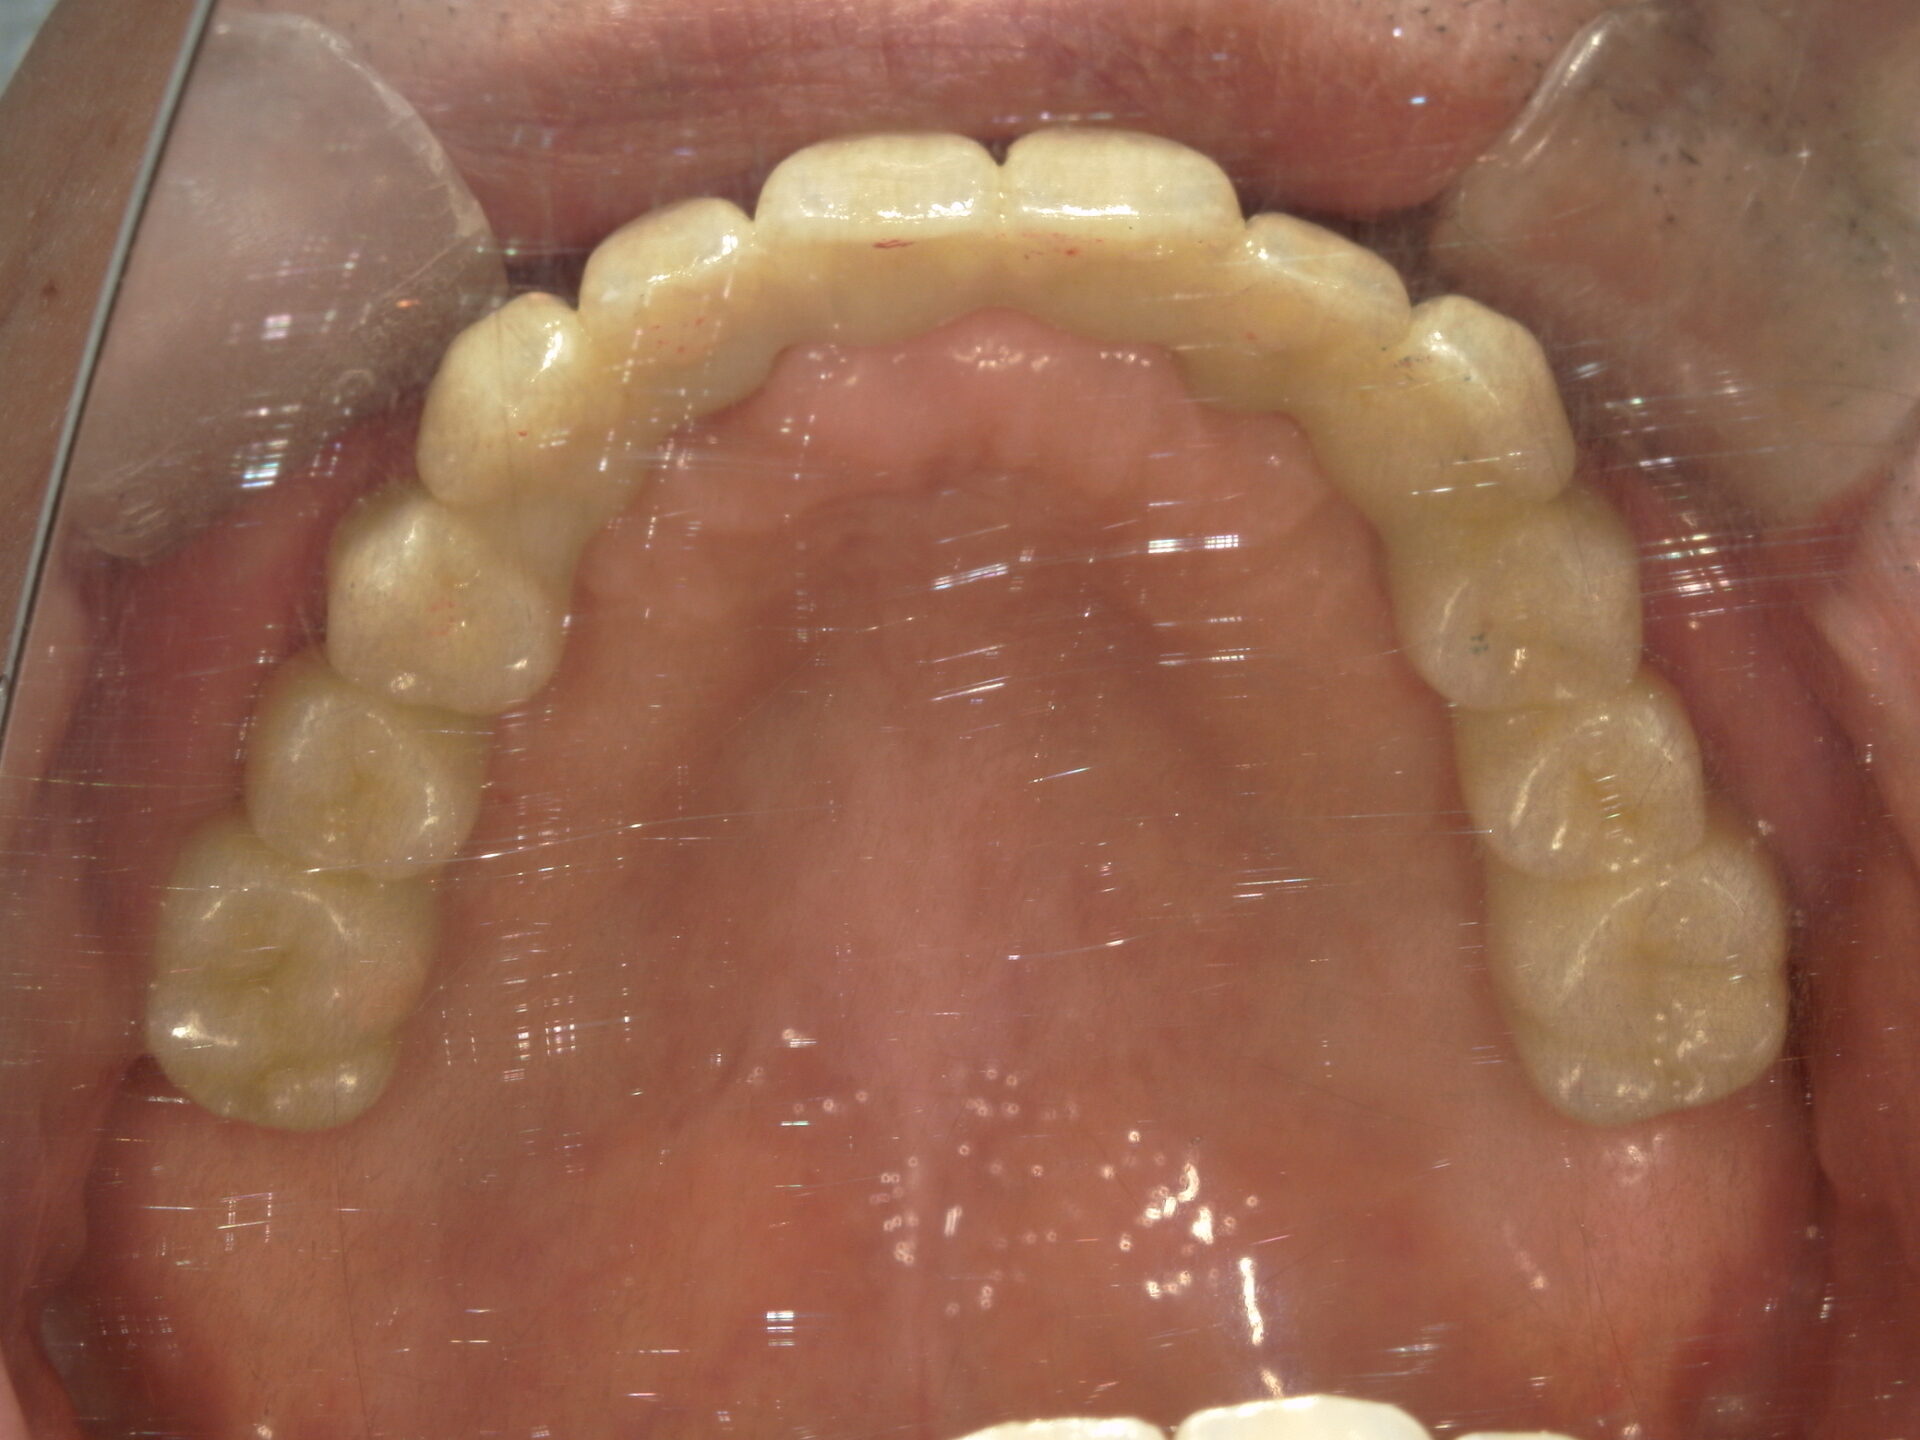

before

患者さんの年齢 50代 男性 症状 何も噛めない 治療内容 インプラント治療(オールオン4) 費用 費用900万(税抜) 治療期間・回数 治療期間2年・通院回数12回 メリット なんでも噛めるようになる 見た目が綺麗 デメリット・リスク 骨造成などで費用が増える場合がある - インプラント治療